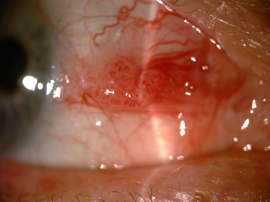

Fig 2. A lesion suspicious for OSSN due to lobulated structure showing abnormal vessel pattern (left) and lissamine green staining (right). Credit: Dr Mo Ziaei

OSSN can range from mild dysplasia to invasive squamous cell carcinoma. Compared to pterygia, lesions suspicious for dysplasia can look more gelatinous, leukoplakic, papilliform or plaque-like and can be more vascularised (presence of a feeder vessel or abnormal blood vessel patterns). Other tests that may help the clinician differentiate between a benign or malignant lesion include the use of Lissamine green staining (Fig 2) or anterior segment OCT examination. There is an abrupt transition from normal epithelium to thickened hyperreflective epithelium in patients with OSSN⁴.